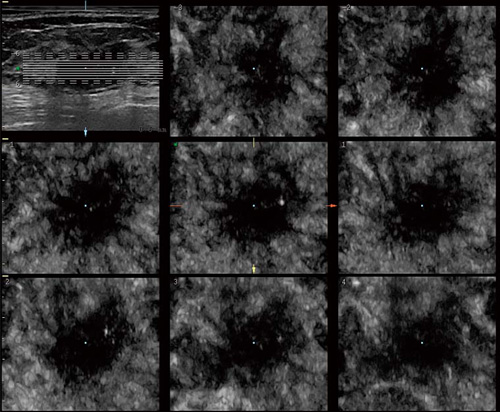

ボリュームデータからは,通常の断面であるA断面,それに直交するB断面,前額断面にあたるC断面を自由に表示可能です。このC断面は,乳がんによる周囲組織の引き攣れの表現に優れ,腫瘍の形態診断に新しい情報を提供します。

Breast Imagingに対するボリュームデータの応用は,C断面に限られたものではありません。直交三断面表示,任意の断面でCTやMRIのように連続断面を表示するTUI,スライス厚を自由に変えてコントラスト分解能を向上させるVCIなど,さまざまなツールが用意されています。

乳がんのC断面におけるTUI像